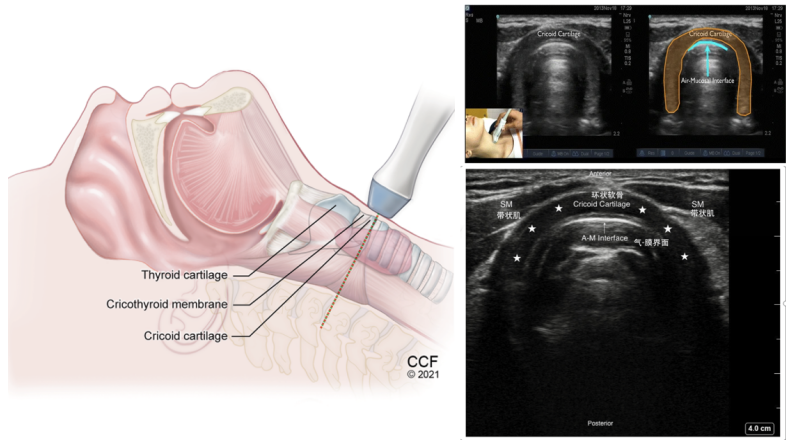

(4)环状软骨横切面:探头继续向下,可以看到倒“U”形或马蹄形结构(图12五角星标注位置),即为环状软骨。环状软骨层面是气道内最狭窄处,在此切面下,可以通过测量气道直径帮助我们选择合适的气管插管。

图片

图12  环状软骨横切面

2. 插管尺寸选择

环状软骨是唯一一个完整的软骨环, 在这个层面, 气道最窄, 我们可以测量气道直径, 据此选择合适的气管插管, 尤其对儿童患者非常重要。